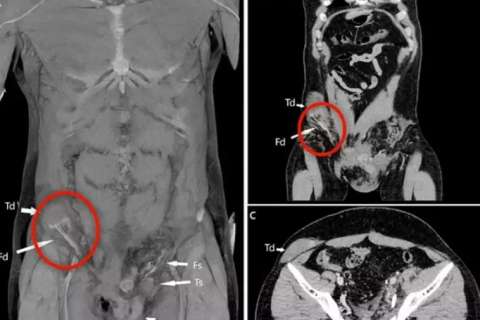

O testículo direito do homem deslocou para o abdômen / Foto: Reprodução

Um italiano teve seu testículo deslocado para o abdômen depois de sofrer um acidente de moto. O caso foi publicado na revista médica BMJ Case Reports em setembro deste ano e divulgado pelo portal Daily Mail.

O testículo direito do homem foi forçado do seu local habitual no saco escrotal através de uma pequena passagem na virilha, subindo até o abdômen. A idade exata da vítima não foi divulgada, apenas que ele tinha por volta dos 20 anos.